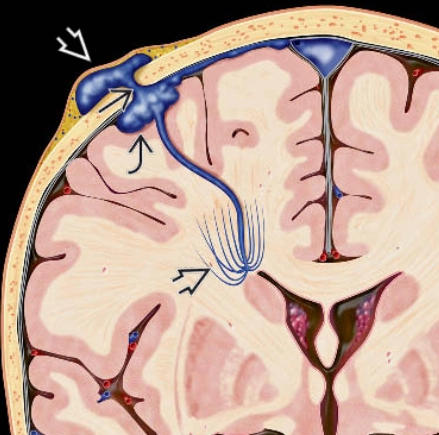

• Xoang màng cứng da đầu (Sinus Pericranii)

Xoang màng cứng da đầu (Sinus Pericranii)